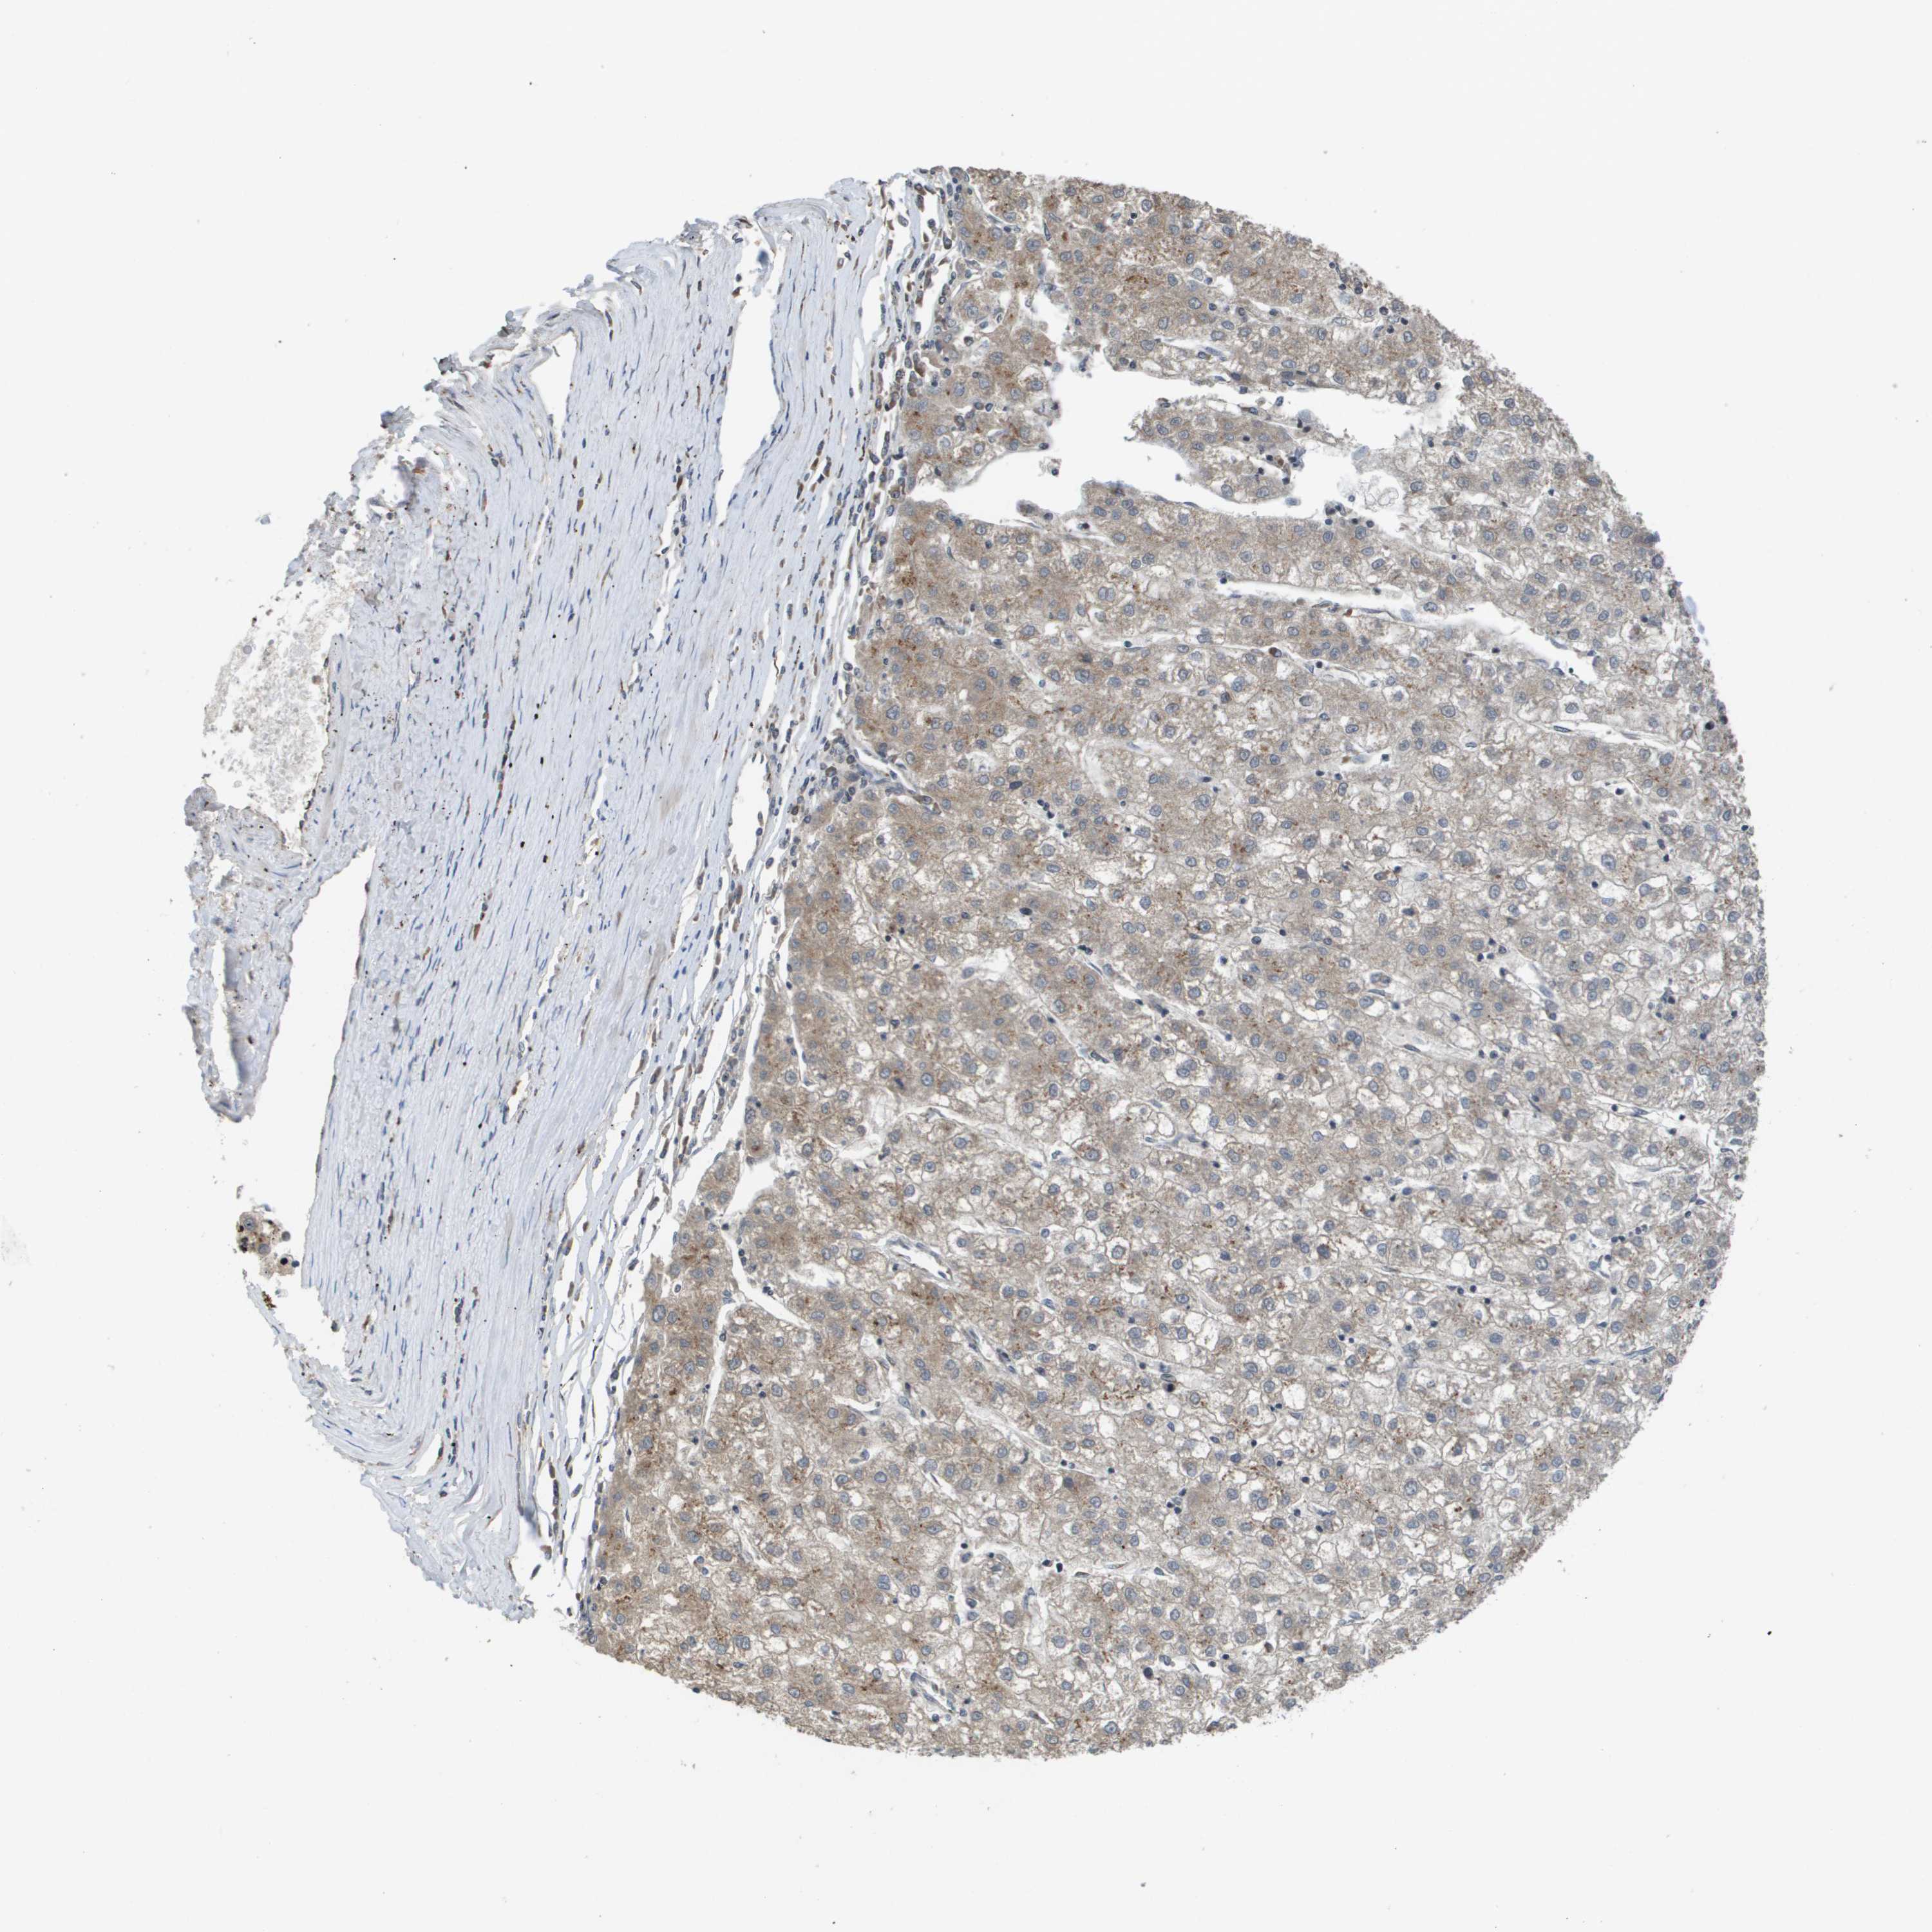

LIVER CANCER - Protein expressioni

A mouse-over function shows sample information and annotation data. Click on an image to view it in a full screen mode. Samples can be filtered based on level of antibody staining by selecting one or several of the following categories: high, medium, low and not detected. The assay and annotation is described here.

Note that samples used for immunohistochemistry by the Human Protein Atlas do not correspond to samples in the TCGA dataset.

Antibody stainingi

Antibody staining in the annotated cell types in the current human tissue is reported as not detected, low, medium, or high, based on conventional immunohistochemistry profiling in selected tissues. This score is based on the combination of the staining intensity and fraction of stained cells.

Each image is clickable and will lead to virtual microscopy that enables deeper exploration of all samples and also displays staining intensity scores, fraction scores and subcellular localization as well as patient and tissue information for each sample.

Antibody HPA006277

Antibody HPA006507

Antibody CAB017027

Staining

High

Medium

Low

Not detected

Intensity

Strong

Moderate

Weak

Negative

Quantity

>75%

75%-25%

<25%

None

Location

Nuclear

Cytoplasmic/membranous

Cytoplasmic/membranous,nuclear

Cholangiocarcinoma

Carcinoma, Hepatocellular, NOS